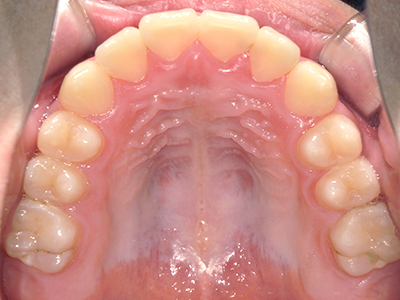

歯並びの相談に来られるお子様は、口呼吸をしているケースが多く、これが歯並びに大きな影響を与えています。

↓ - 頬の圧力が上の歯列にかかりやすくなる

↓ - 上あごが狭くなる

↓ - 下あごが狭くなる・下あごの位置が悪くなる

↓ - さまざまな不正咬合が生じる

ないき歯科クリニックでは、上あごの成長不足を補い、鼻呼吸を獲得しつつ歯列を整え、将来のお口をより健康な状態にすることをゴールに定める矯正治療をおこなっています。